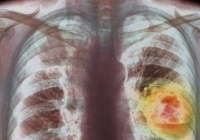

Khó thở là triệu chứng dễ nhận thấy của bệnh phổi tắc nghẽn mãn tính (Ảnh: Internet)